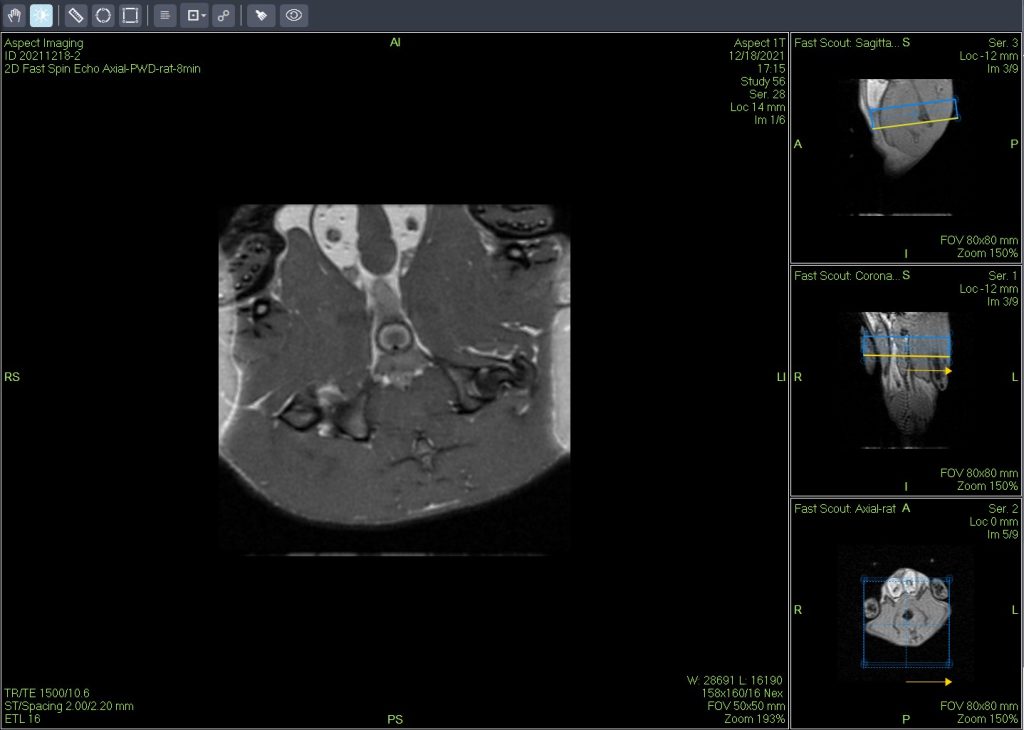

活體磁共振成像在模型小鼠中檢測到局灶性肝損傷(圖A)。肝臟的高分辨率離體MRH評估可以在小鼠(圖B和C)中鑒定幾個單獨的局灶性脂肪病變。通過常規組織病理學證實病變為局灶性脂肪改變(圖C)。